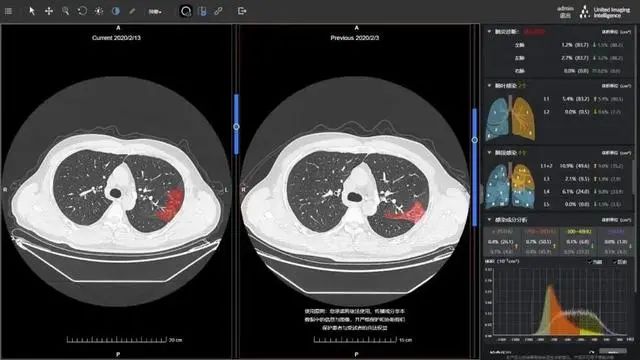

图1  肺炎CT影像AI辅助诊断软件分析

图片来源:《财经》杂志:AI“独角兽”受挫医学影像,谁能从医院手里挣到钱?